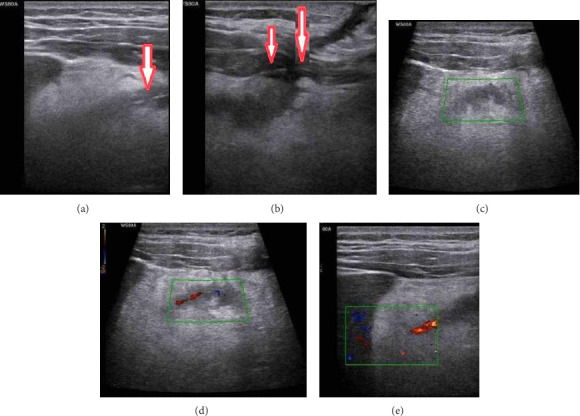

Background: Retained sutures following catheterization procedures are rare but can present significant diagnostic and therapeutic challenges. This case highlights a novel approach to diagnosing and managing a retained anchoring suture following catheter removal for abdominal fluid drainage in a patient with pancreatic adenocarcinoma and metastatic ascites. The use of color Doppler ultrasound to identify the suture's path and the application of the retract-and-cut technique minimized invasive interventions, demonstrating a safe and effective alternative to surgical removal. Case Presentation: A 68-year-old male with pancreatic adenocarcinoma and metastatic ascites underwent subhepatic fluid drainage using an 8Fr pigtail catheter. After successful drainage and catheter removal, the patient presented with localized pain and tenderness at the catheter insertion site. Ultrasound revealed a hyperechoic linear structure in the subcutaneous tissue suggestive of a retained suture. Real-time visualization using color Doppler ultrasound confirmed the suture's path as a linear Doppler signal was observed during manipulation. Given the adhesion of the suture to deeper tissues, the retract-and-cut technique was employed. The suture was gently pulled taut at the skin surface, cut, and allowed to retract along its original track, avoiding unnecessary trauma. The patient experienced no recurrence of symptoms, fluid collection, or infection during long-term follow-up. Conclusions: This case underscores the importance of timely diagnosis using color Doppler ultrasound, which provided real-time visualization of the retained suture and its relationship with surrounding tissues. In addition, the retract-and-cut technique offers a minimally invasive and effective approach for managing retained sutures, avoiding the need for surgical intervention. This method ensures patient comfort and safety, particularly in palliative care settings where nonsurgical options are prioritized.